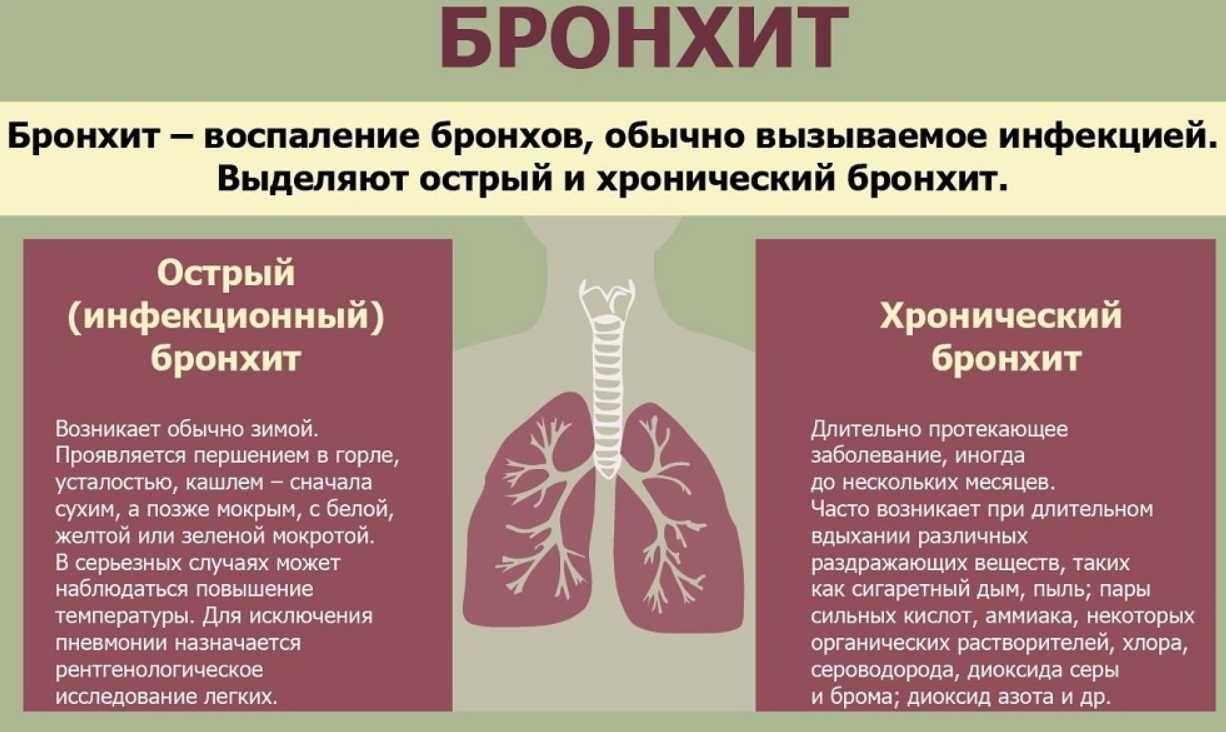

Бронхит – заболевание дыхательной системы, при котором происходят воспалительные процессы в бронхиальном дереве. Одни из основных признаков болезни — значительное повышение температуры тела и кашель. Но иногда бывает и бессимптомное течение бронхита. Как диагностировать его в этом случае и какие методы лечения использовать, узнайте далее.

Виды бронхита без температуры

Существует несколько форм бронхита, при которых температура тела чаще всего держится в пределах нормы. К ним относятся:

Острый бронхит, проявляющийся как осложнение других болезней дыхательной системы, всегда сопровождается повышением температуры тела.